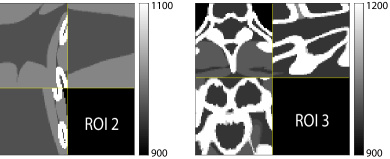

Fig. 4 shows the reconstructed images and the corresponding error images for PWLS-EP, PWLS-ULTRA, and SPULTRA, at and . Compared to the PWLS-EP result, both PWLS-ULTRA and SPULTRA achieved significant improvements in image quality in terms of sharper reconstructions of anatomical structures such as bones and soft tissues, and suppressing the noise. However, the PWLS-ULTRA method introduces bias in the reconstructions, which leads to larger reconstruction errors compared to the proposed SPULTRA method. In Fig. 4, we marked three 3D ROIs in the axial plane, i.e., ROI 1, ROI 2, and ROI 3. Fig. 5 shows the zoom-in images of a 3D plot of ROI 1, and those of ROI 2 and ROI 3 are shown in the supplement. We also plot the evolution of RMSE through the axial slices of the three 3D ROIs in Fig. 6. The figures demonstrate that SPULTRA clearly outperforms the competing PWLS-EP and PWLS-ULTRA schemes.

Fig. 14 and Fig. 15 plot the zoom-ins and the corresponding error images of ROI 2 and ROI 3 for the XCAT phantom simulations in Section V.A, with and , respectively. In Fig. 15, we highlighted a region in the axial slice with small red arrows. We show the zoom-ins of the ground-truth ROI 2 and ROI 3 of the XCAT phantom in Fig. 16. The results show that SPULTRA improves image quality over PWLS-EP and PWLS-ULTRA by reducing bias and improving image edges.